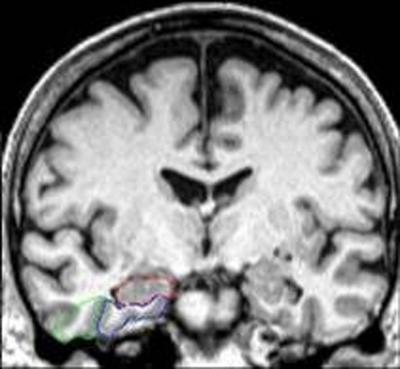

Researchers used a fluorescent molecule to track live guanosine triphosphate levels in neurons from aged mice showing signs of Alzheimer’s.

Scientists found that the levels of energy-rich molecules GTP declined with age – particularly in the cells’ mitochondria – leading to impaired elimination of cells with damaged components in a process called autophagy.

However, the findings point to promising strategies to rescue neurons in the brain’s hippocampus from energy deficits related to ageing and Alzheimer’s disease, researchers say.